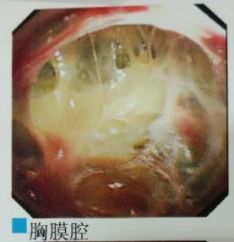

蜘蛛网胸水(包裹性胸腔积液),在胸腔镜下是什么鬼样子的呢?

且看胸腔镜:

胸腔里面这么多分隔,你能保证你的针在哪个小分隔里面?除非你有孙悟空的火眼金睛!

在胸腔镜下,是“蜘蛛网+蜂窝状”般的变态存在。

你说说,这种情况怎么愉快的抽胸水?

大招:胸腔镜下,用活检钳,把分隔剪断,放粗管。当然,有可能:剪不断,理还乱。